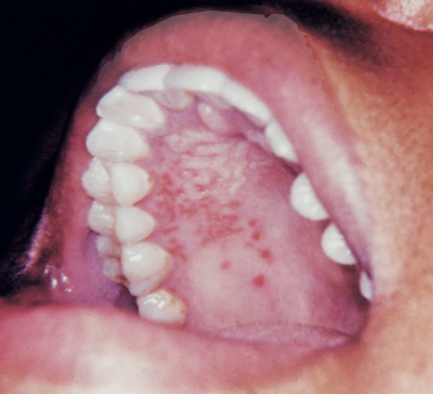

On examination, he is alert and speaking in full sentences. Temperature is 38.4°C. There is tender cervical lymphadenopathy. Oropharyngeal examination shows an erythematous pharynx with patchy exudate. The accompanying image is provided :

What is the most likely diagnosis?